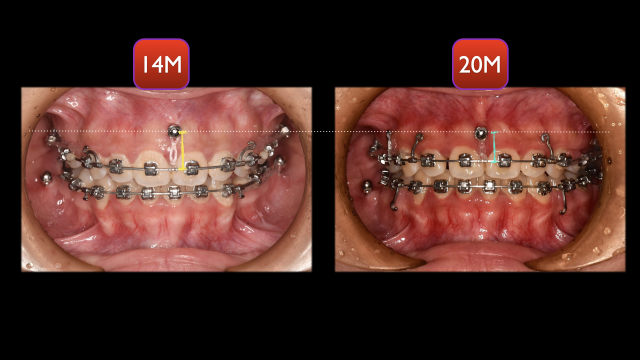

术中治疗